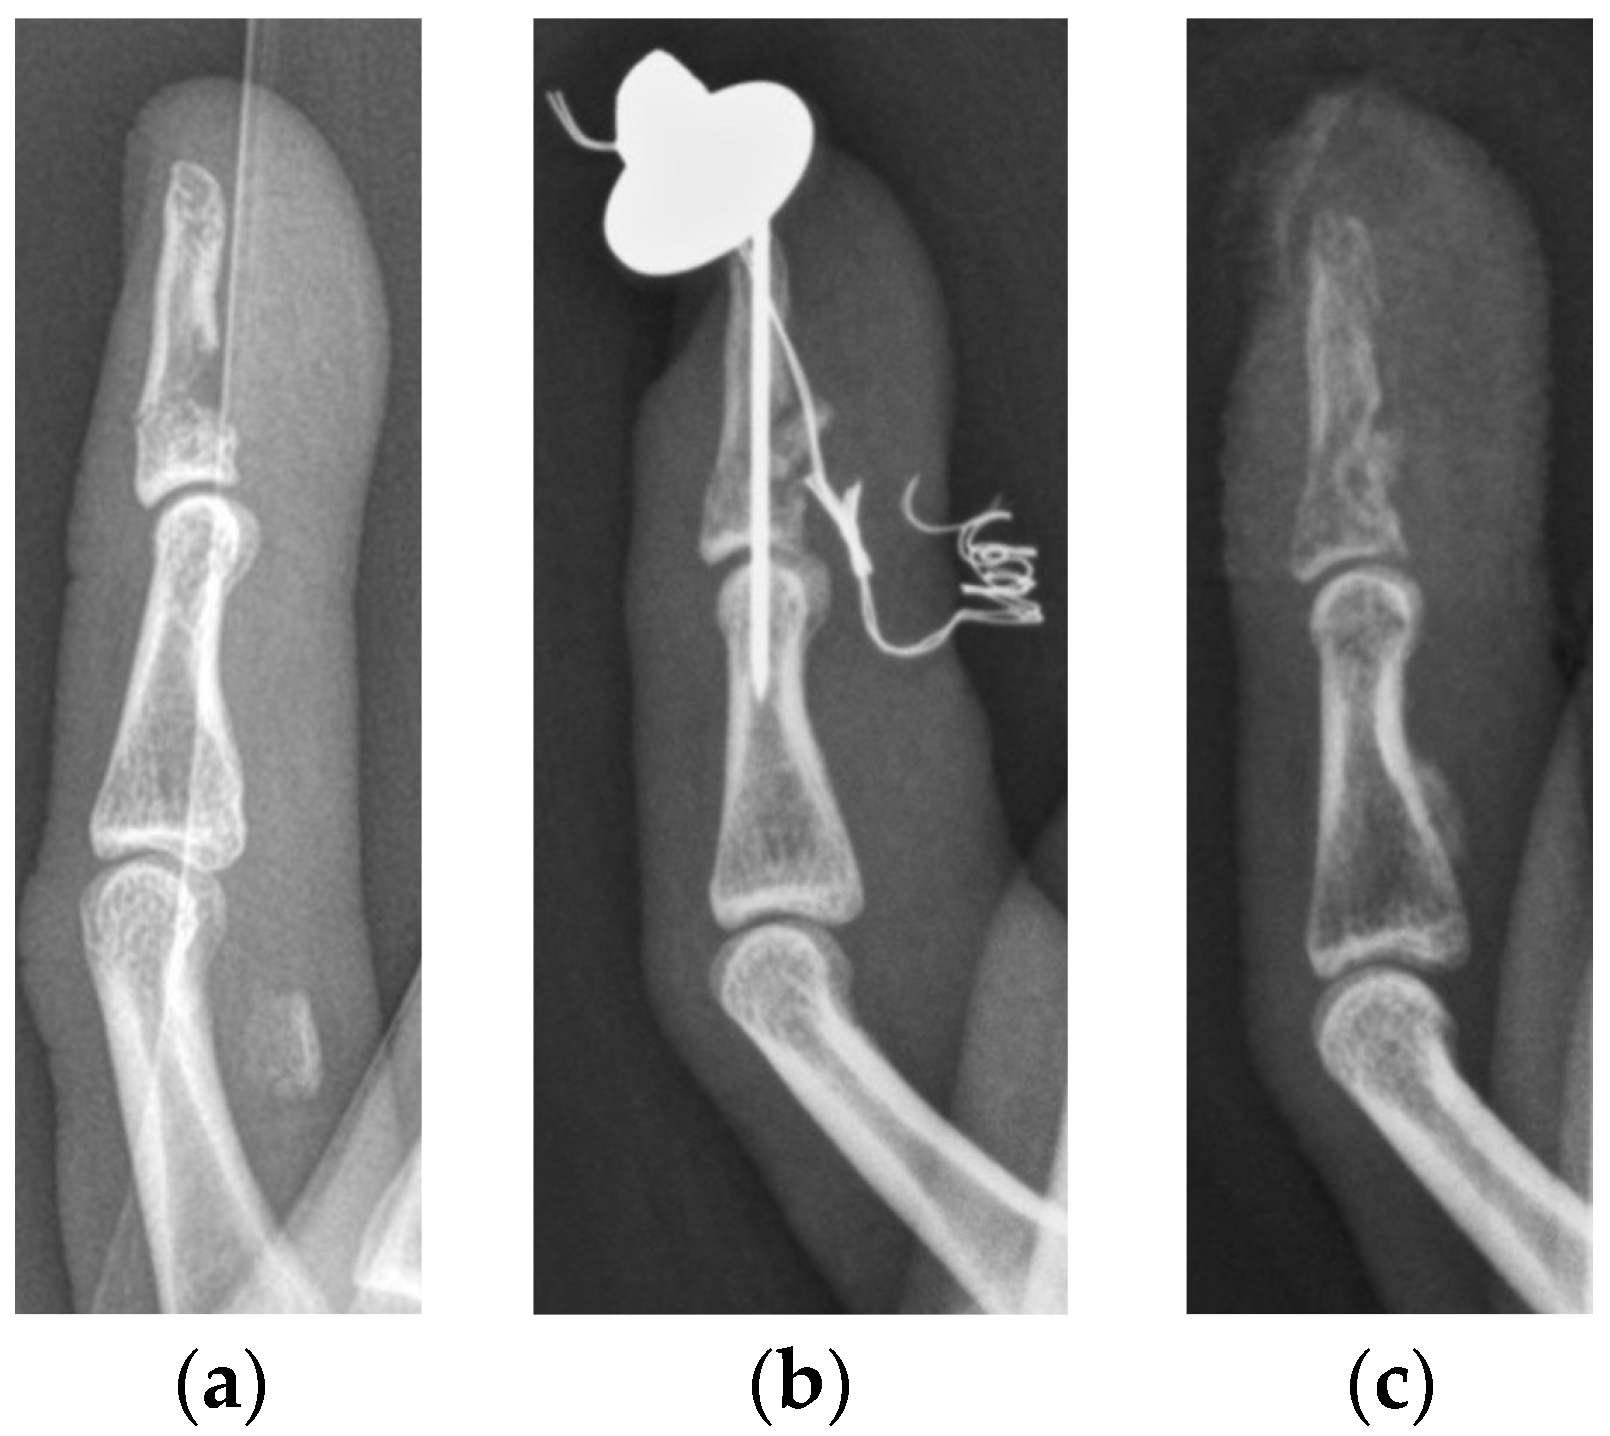

Figure 2. Lateral radiographs of a minimally displaced type Va (a) and type Vb (b) jersey finger, treated conservatively in our department.

All medical records of the patients, including the discharge summaries, as well as diagnostic, therapeutic and operative reports, together with radiographic, CT and MR images, were included in the evaluation of the patients for this study. All images were analyzed using an IMPAX workstation (Agfa, Ridgefield Park, NJ, USA). Due to calibration of magnification and distances of performed medical imaging, exact distance measurements were facilitated. All patients were analyzed in the corresponding jersey finger subtype group. Furthermore, we subdivided the patient cohort into two subgroups: (1) severe displaced (SD), matching at least one indication for surgery as mentioned above, and (2) minimally displaced (MD) injuries (Figure 2).